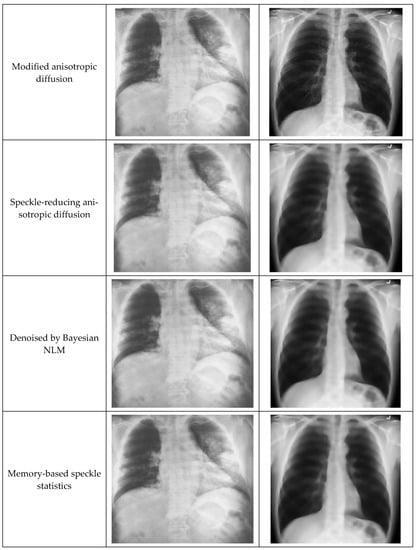

Filtering techniques preserve useful information while filtering any noise within an image. To extract the meaningful features of any noisy image, the information-preserving filtering techniques are most applicable [21]. During the testing phase, speckle-affected test images were used to assess filtering performance. Anisotropic diffusion filtering can preserve and enhance edge information while subduing any noise [24,47]. The gradient operator detects the edge information along with noise [48]. This technique finds the gradient changes in noise for strong speckle and low contrast images, which may go beyond the gradient of edge. These changes destruct the edge information than the noise, which provides less accuracy in filtering results. Similarly, speckle reducing anisotropic diffusion (SRAD) cannot fully preserve the edge information due to image over-smoothing [49]. Oriented-based non-local means (OBNLM) fails to hold detailed information and is affected by moving noise [27]. Anisotropic diffusion with memory-based speckle statistic (ADMSS) is sharper in white pixels [50].

Modified anisotropic diffusion filtering (MADF) was proposed for this work in order to preserve detailed information while reducing noise and distortion from the images. This filtering technique performs better than the other filtering methods due to its capability in eliminating multiplicative speckle noise in plane regions. The proposed method uses correlation and kurtosis values of noise to hold the useful edge information. In Equation (2), Io is a noisy image comprised of speckle-noise n and the original image I [27,49]. The noise part is denoted by Equation (3), where G is noise intensity and calculated from image properties in MATLAB. The mean of noise intensity is µ, which is calculated by Equation (4). Kurtosis k is calculated using Equation (5). The correlation between the image class and noise class should be minimum, which is the iteration stopping condition. This speckle suppression process continues until the noise part of the image is close to the Gaussian value. In this situation, the kurtosis value should be zero. The iteration cutoff is defined when the kurtosis value falls below 0.001 (Equation (6)), indicating a low speckle with better edge preservation. As soon as the correlation between image class and noise class is the least, the iteration will be stopped. Equation (7) calculates the correlation of image intensities

() and Equation (8) calculates the correlation of noise intensities (). The proposed filtering will get the optimal result when and show minimum deviance.

Figure 5 shows an example of original images and a comparison of different Anisotropic Diffusion techniques. It was very clear that the edge preservation capability of the proposed MADF technique was much better than the other techniques.

Figure 5.

Illustration of images after applying different anisotropic diffusion techniques.

Upon applying MADF, the images are divided into multiple small parts of images, which is called a gradient. Then these parts are filtered one-by-one. After filtering all parts, they are merged together. In general, the anisotropic diffusion filtering method removes all noises and edge information from the images. If this method is applied to the image with many iterations, the edge information in the images is removed. If the k value is 0, then all image features or in-formation is removed. Therefore, filtering continues up to a standard k value of 0.001 in order to obtain an appropriate filtered image. In general, it is quite difficult to ex-tract appropriate features from the blur images, whereas the MADF method solves this issue.